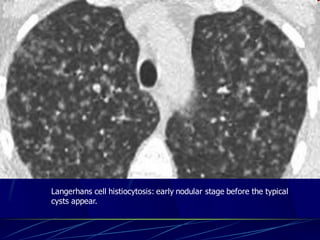

Random distribution

Small random nodules

are seen in:

 Hematogenous

metastases

 Miliary tuberculosis

 Miliary fungal infections

 Sarcoidosis may mimick

this pattern, when very

extensive

 Langerhans cell

histiocytosis (early

nodular stage)

Langerhans cell histiocytosis: early nodular stage before the typical

cysts appear.